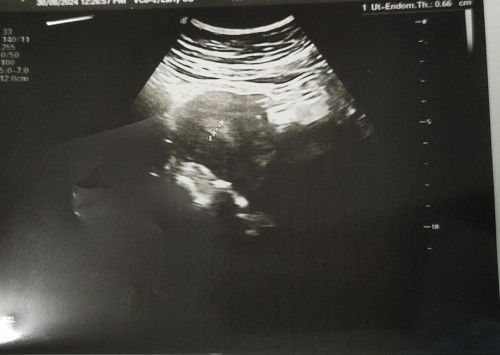

Normal ke 8w blum nmpak apa2,sbb baru2 ni sy bleeding mcm period 5hari

Dah p jumpa doc n scan,dinding rahim masih tebal..tp buat ujian air kencing -ve..doc kata slalunya kes mcm ni test akn +ve..sy akn repeat scan 14/9 nnty..risau plak sy..ada ibu2 dlm ni ada pengalaman mcm ni x..sbb sy xda lgsung rasa mual nk muntah or morning sickness mcm ibu2 baru preggy kt luar sana..normal ke.. #1stpreggy #1stmom